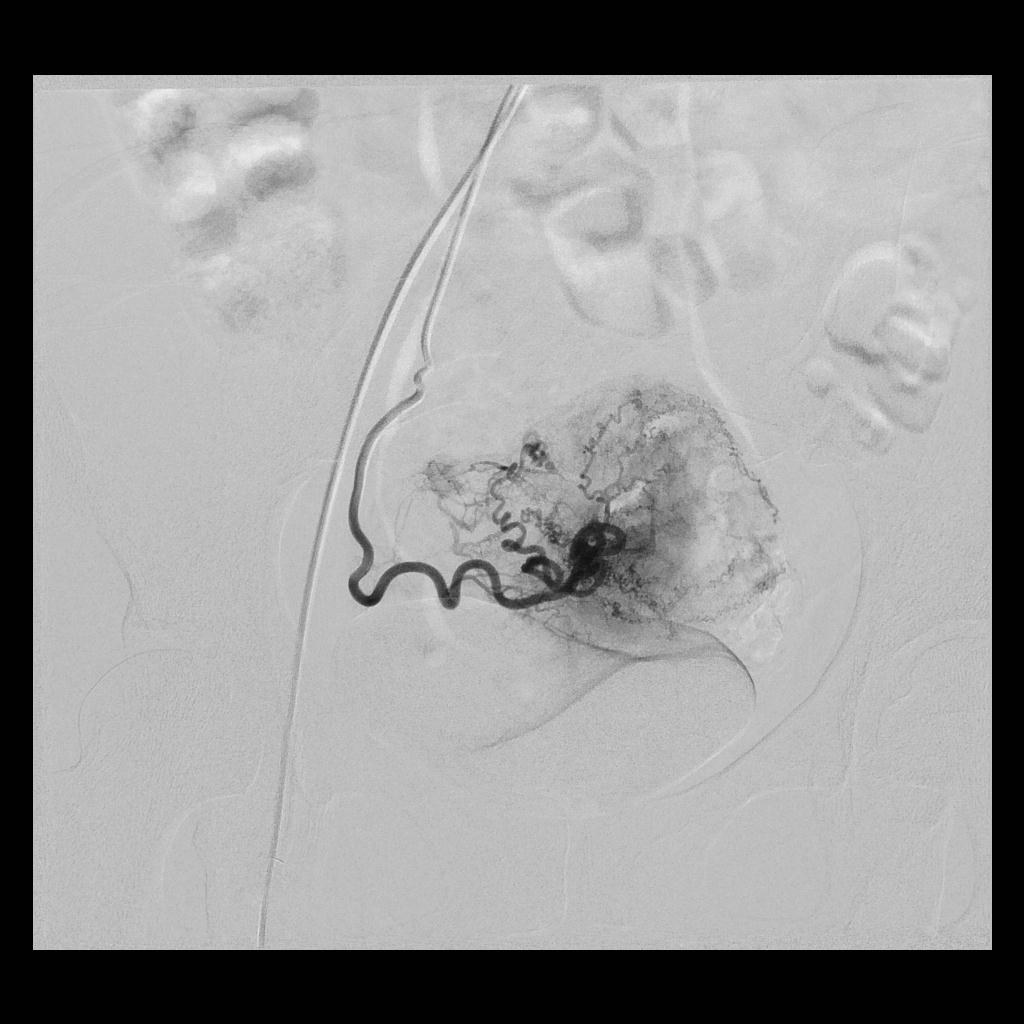

后经腹部主动脉造影显示,子宫双侧的子宫动脉均有增粗、迂曲的情况(下图中红色箭头所示),子宫和子宫肌瘤也均有所增大(下图中绿圈所示)

(左侧子宫动脉造影:术前、术后)

(右侧子宫动脉造影:术前、术后)